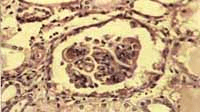

Se hospitalizó y se ordenó dieta hiposódica, restricción de líquidos, prednisona, 25 mg/día, y captopril 0.3 mg/k/d, Los controles posteriores mostraron cifras tensionales que oscilaron entre 135/90 y 120/80 y la FC entre 80 y 90 x min. Se añadió furosemida y se subió dosis de prednisona 60 mg/día. Otras pruebas mostraron ANAS+ 1:640; biopsia de piel con perivasculitis superficial y estudio de inmunofluorescencia con depósitos granulares en membrana basal de lgG, lgM, Cl q y trazas de C3; biopsia renal con proliferación mesangial, asas de alambre, lobulación, medias lunas epiteliales y esclerosis del 10% de los glomérulos, inmunofluorescencia con depósitos mesangiales granulares de lgG, lgM, C3 C4 C1q. Se interpretó como una glomerulonefritis mesangiocapilar de tipo lúpico clase IV. Figuras No 1, 2 y 3. Se inició terapia con ciclofosfamida Los controles mostraron cifras de BUN de 67 y Creatinina de 1, que descendieron 6 días después a 20 y 0.6 respectivamente.

Figura No 1. Micofotografia de la biopsia renal con un glomérulo hipercelular,

con formación de medialuna. HE 10x